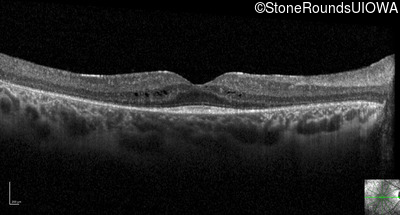

Visit at age: 21 years

Optical Coherence Tomography - Left - 20/32

Exemplar / OCT Stack